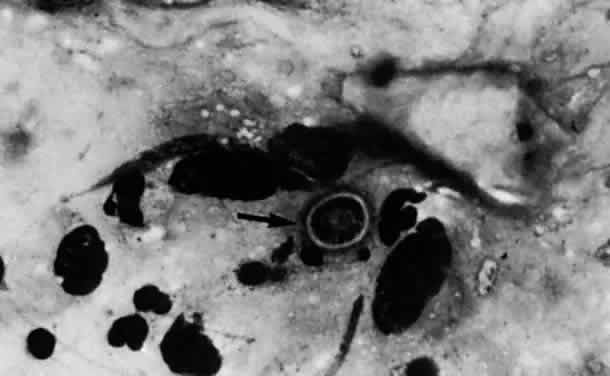

Acanthamoeba organisms are small and resilient, with a wide distribution in the environment.1,2 The protozoan's life cycle is characterized by a transformation from active trophozoite to dormant cyst. The irregularly shaped trophozoite, which is 15 to 45 μm in diameter, is slowly motile (Fig. 1). The cyst is 10 to 25 μm long and has a thick double-walled external structure consisting of an outer wrinkled ectocyst and inner polygonal endocyst (Fig. 2).3,4 Transformation from the trophozoite to the cyst stage enhances survival in unfavorable circumstances, which include wide temperature ranges, desiccation, food depletion, pH changes, low oxygen concentration, and cell crowding.5

Fig. 2. Characteristic polygonal Acanthamoeba cyst.